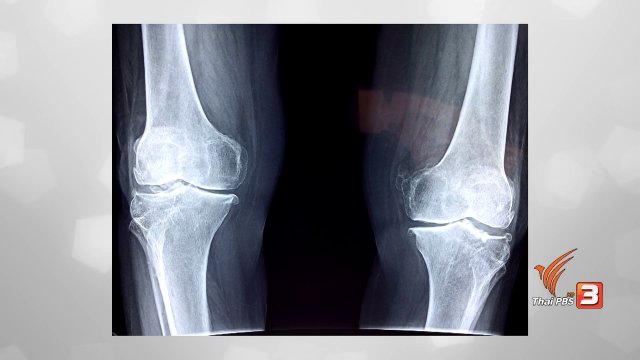

ปรับก่อนป่วย : 5 เทคนิคดูแลตัวเอง ป้องกันข้อเข่าเสื่อม

ปรับก่อนป่วย : กายภาพบำบัดแก้อาการข้อเข่าเสื่อม